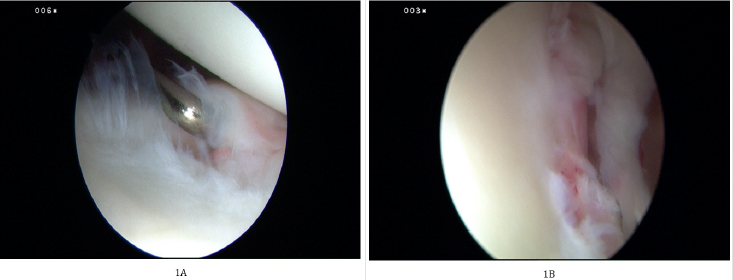

Postoperatively an arm sling was used to immobilize the shoulder up to four weeks. After six weeks, active exercise under physiotherapy guidance was allowed, and external rotation allowed after nine weeks. The return to full sporting activities was allowed after six months. In our study, we had 49 male patients (94.2%) and three female patients (5.8%). Twenty-one were left-handed (40.4%), and 31 were right-handed (59.6 %). The mean age of our patient at first dislocation was 25.3, and the mean age when they had the operation was at 27.2 (Figure 1).

Figure 1:

A. Showing a Bankart lesion post traumatic shoulder dislocation,

B. Shows probe used to assess the integrity of the labrum before debridement and suture passing.